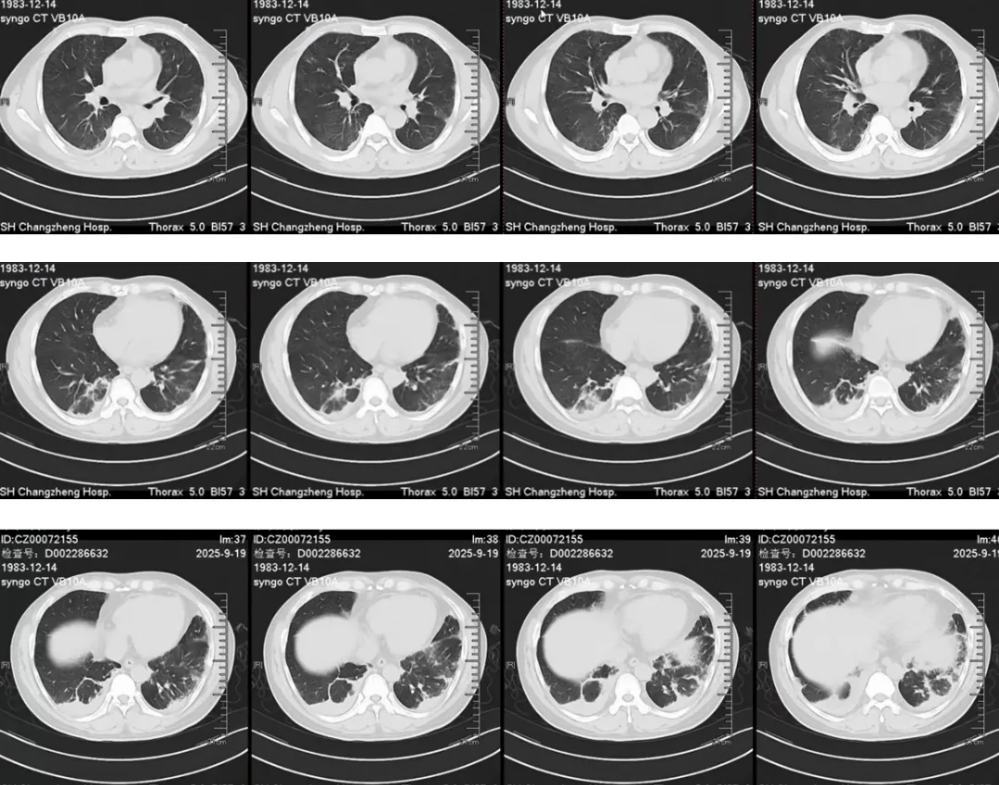

胸部CT(2025-9-18):双肺多发炎症,纵隔内及双侧腋窝见多发稍大淋巴结影,心隔角肿大淋巴结,双侧胸腔少量积液(图见后)。

胸部CT(2025-9-18)

影像表现:双肺间质和肺泡浸润影,HRCT显示边界不清的磨玻璃结节(100%)和小叶间隔增厚(90%),双侧胸腔积液(76%),气体陷闭(55%)。

影像表现:双肺、弥漫、上肺外周分布(25%)、边界不清、游走性,对激素治疗敏感,空洞少见。

胸部影像:肺部浸润影(50%-70%),边界不清、密度不均、外周或随机分布、可游走,对激素治疗敏感;小叶中心结节、支气管壁增厚、支气管扩张;小叶间隔增厚、纵膈淋巴结肿大、胸水、心包积液。 实验室检查:外周血嗜酸细胞百分比>25%,通常>40%,40%患者p-ANCA阳性,阴性不能排除诊断,抗体滴度与病情无关。